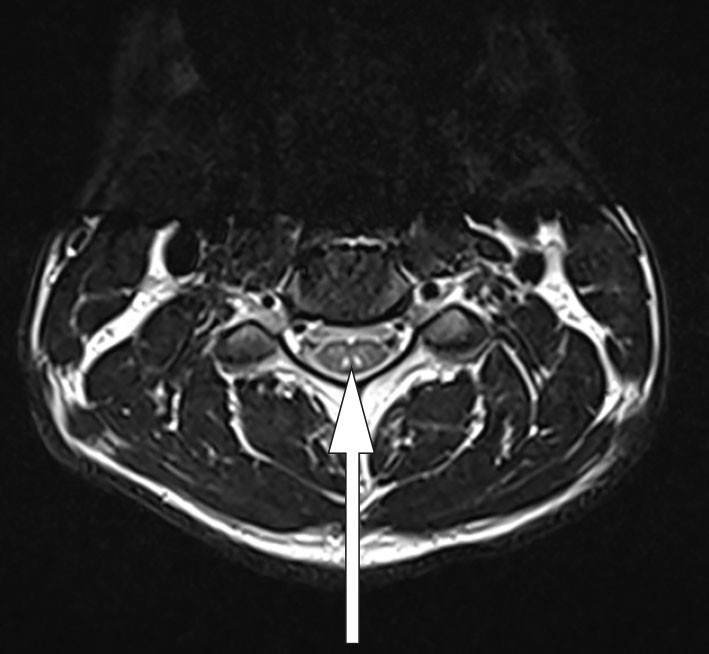

Ved kontrastforsterket MR-undersøkelse av sentralnervesystemet dag 5 viste T2-vektet bilde et subtilt høysignal i medulla på C2/C3-nivå på sagittale snitt (figur 1), og det var kontrastopplading tilsvarende bakstrengen på aksiale snitt (figur 2). Derimot var det ingen kontrastopptak langs lumbale nerverøtter eller conus medullaris.

Funnene tydet på nerveskader både i medulla og i underekstremitetene. Ettersom det ikke var forhøyet protein i spinalvæsken eller kontrastopplading lumbalt på MR-undersøkelse, var funnene ikke forenlig med Guillain-Barrés syndrom. MR-undersøkelse av ryggmargen (figur 2) viste såkalt omvendt V-tegn (inverted V-sign) eller «kaninører». Dette er benevnt som subakutt kombinert degenerasjon og er karakteristisk for demyelinisering av bakstrengen på bakgrunn av B12-mangel (5).